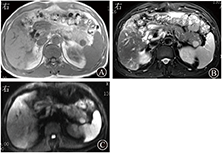

患者男,52岁,因乏力、纳差、尿黄7 d入院。患病以来胃纳明显减退,无腹痛、腹泻、恶心、呕吐、胸闷、气急等。门诊检查肝功能:TBil为33.7 μmol/L,DBil为17.9 μmol/L,ALT为73 U/L,AST为249 U/L。10年前曾行胆囊切除术,有戊型肝炎史。于2014年11月27日以慢性肝病收入院。体格检查:体温36.8 ℃,脉搏77次/min,呼吸19次/min,血压115/75 mmHg(1 mmHg=0.133 kPa)。皮肤、巩膜轻度黄染,浅表淋巴结无肿大,全身未见蜘蛛痣,未见肝掌。两肺呼吸音清,未闻及干、湿性啰音。心律齐,未闻及病理性杂音。全腹平软,腹壁无曲张静脉,全腹无压痛及反跳痛,肝区叩击痛阳性,肝脾肋下未及,墨菲征阴性,移动性浊音阴性,肠鸣音无亢进,双下肢无水肿。上腹部CT示,胰腺尾部一直径为1.2 cm类圆形病灶,平扫与胰腺等密度,动脉期病灶强化较胰腺低,呈不均匀强化,门静脉期强化均匀,与胰腺等密度(图1)。MRI示,胰尾部一直径1.2 cm类圆形病灶,T1加权像呈均匀低信号,T2加权像、弥散加权成像呈高信号,表观弥散系数呈低信号,在所有扫描序列与主脾信号相似,动脉期呈不均匀强化,门静脉期呈均匀强化(图2)。AFP、CEA正常,CA19-9 49.4 U/mL(参考范围为0~39 U/mL),烯醇化酶21.1 μg/L(参考范围为0~12.5 μg/L)。入院后给予复方甘草酸苷、丁二磺酸腺苷甲硫氨酸、熊去氧胆酸护肝退黄利胆治疗,于2014年12月22日在全身麻醉下行腹腔镜胰尾肿瘤+脾切除术,术后病理报告胰尾异位脾。

胰腺内异位副脾影像学通常表现为胰尾部光滑圆形、类圆形或浅分叶肿块,边界清楚。CT平扫表现为等密度或稍低密度,增强动脉期不均匀强化,门静脉期、延迟期强化均匀,与脾强化相似。MRI所有序列信号特点与主脾相似,与正常胰腺实质相比,T1加权像呈低信号,T2加权像呈高信号,弥散加权成像呈高信号,增强强化特点与CT相似,表现为动脉期不均匀强化,门静脉期、延迟期均匀强化。使用超顺磁氧化颗粒特异性MRI对比剂可提高胰腺内异位副脾的诊断准确性。胰腺内异位副脾典型影像学诊断并不困难,但主脾切除后或异位副脾内合并表皮样囊肿时会给诊断带来难度。因囊肿内壁光滑,所以寻找囊肿周围副脾组织是诊断关键[2] 。胰腺内异位副脾还需与胰尾部富血供肿瘤鉴别。胰腺囊实性乳头状瘤好发于20~40岁女性,有完整包膜,肿瘤内囊变、出血常见;CT、MRI示肿瘤内部密度、信号不均,MRI可显示肿瘤边缘低信号。胰腺神经内分泌肿瘤因具有特征性临床表现,易被早期发现,肿瘤体积较小,增强动脉期均匀强化或环形强化,门静脉期强化等于或低于胰腺。黑色素瘤、平滑肌肉瘤、肾癌等胰尾转移性肿瘤常表现为富血供,平扫肿瘤呈低密度,增强表现为动脉期不均匀强化,门静脉期强化常低于胰腺。与富血供肿瘤鉴别困难时,超顺磁氧化颗粒信号减低可有助胰腺内异位副脾的诊断。